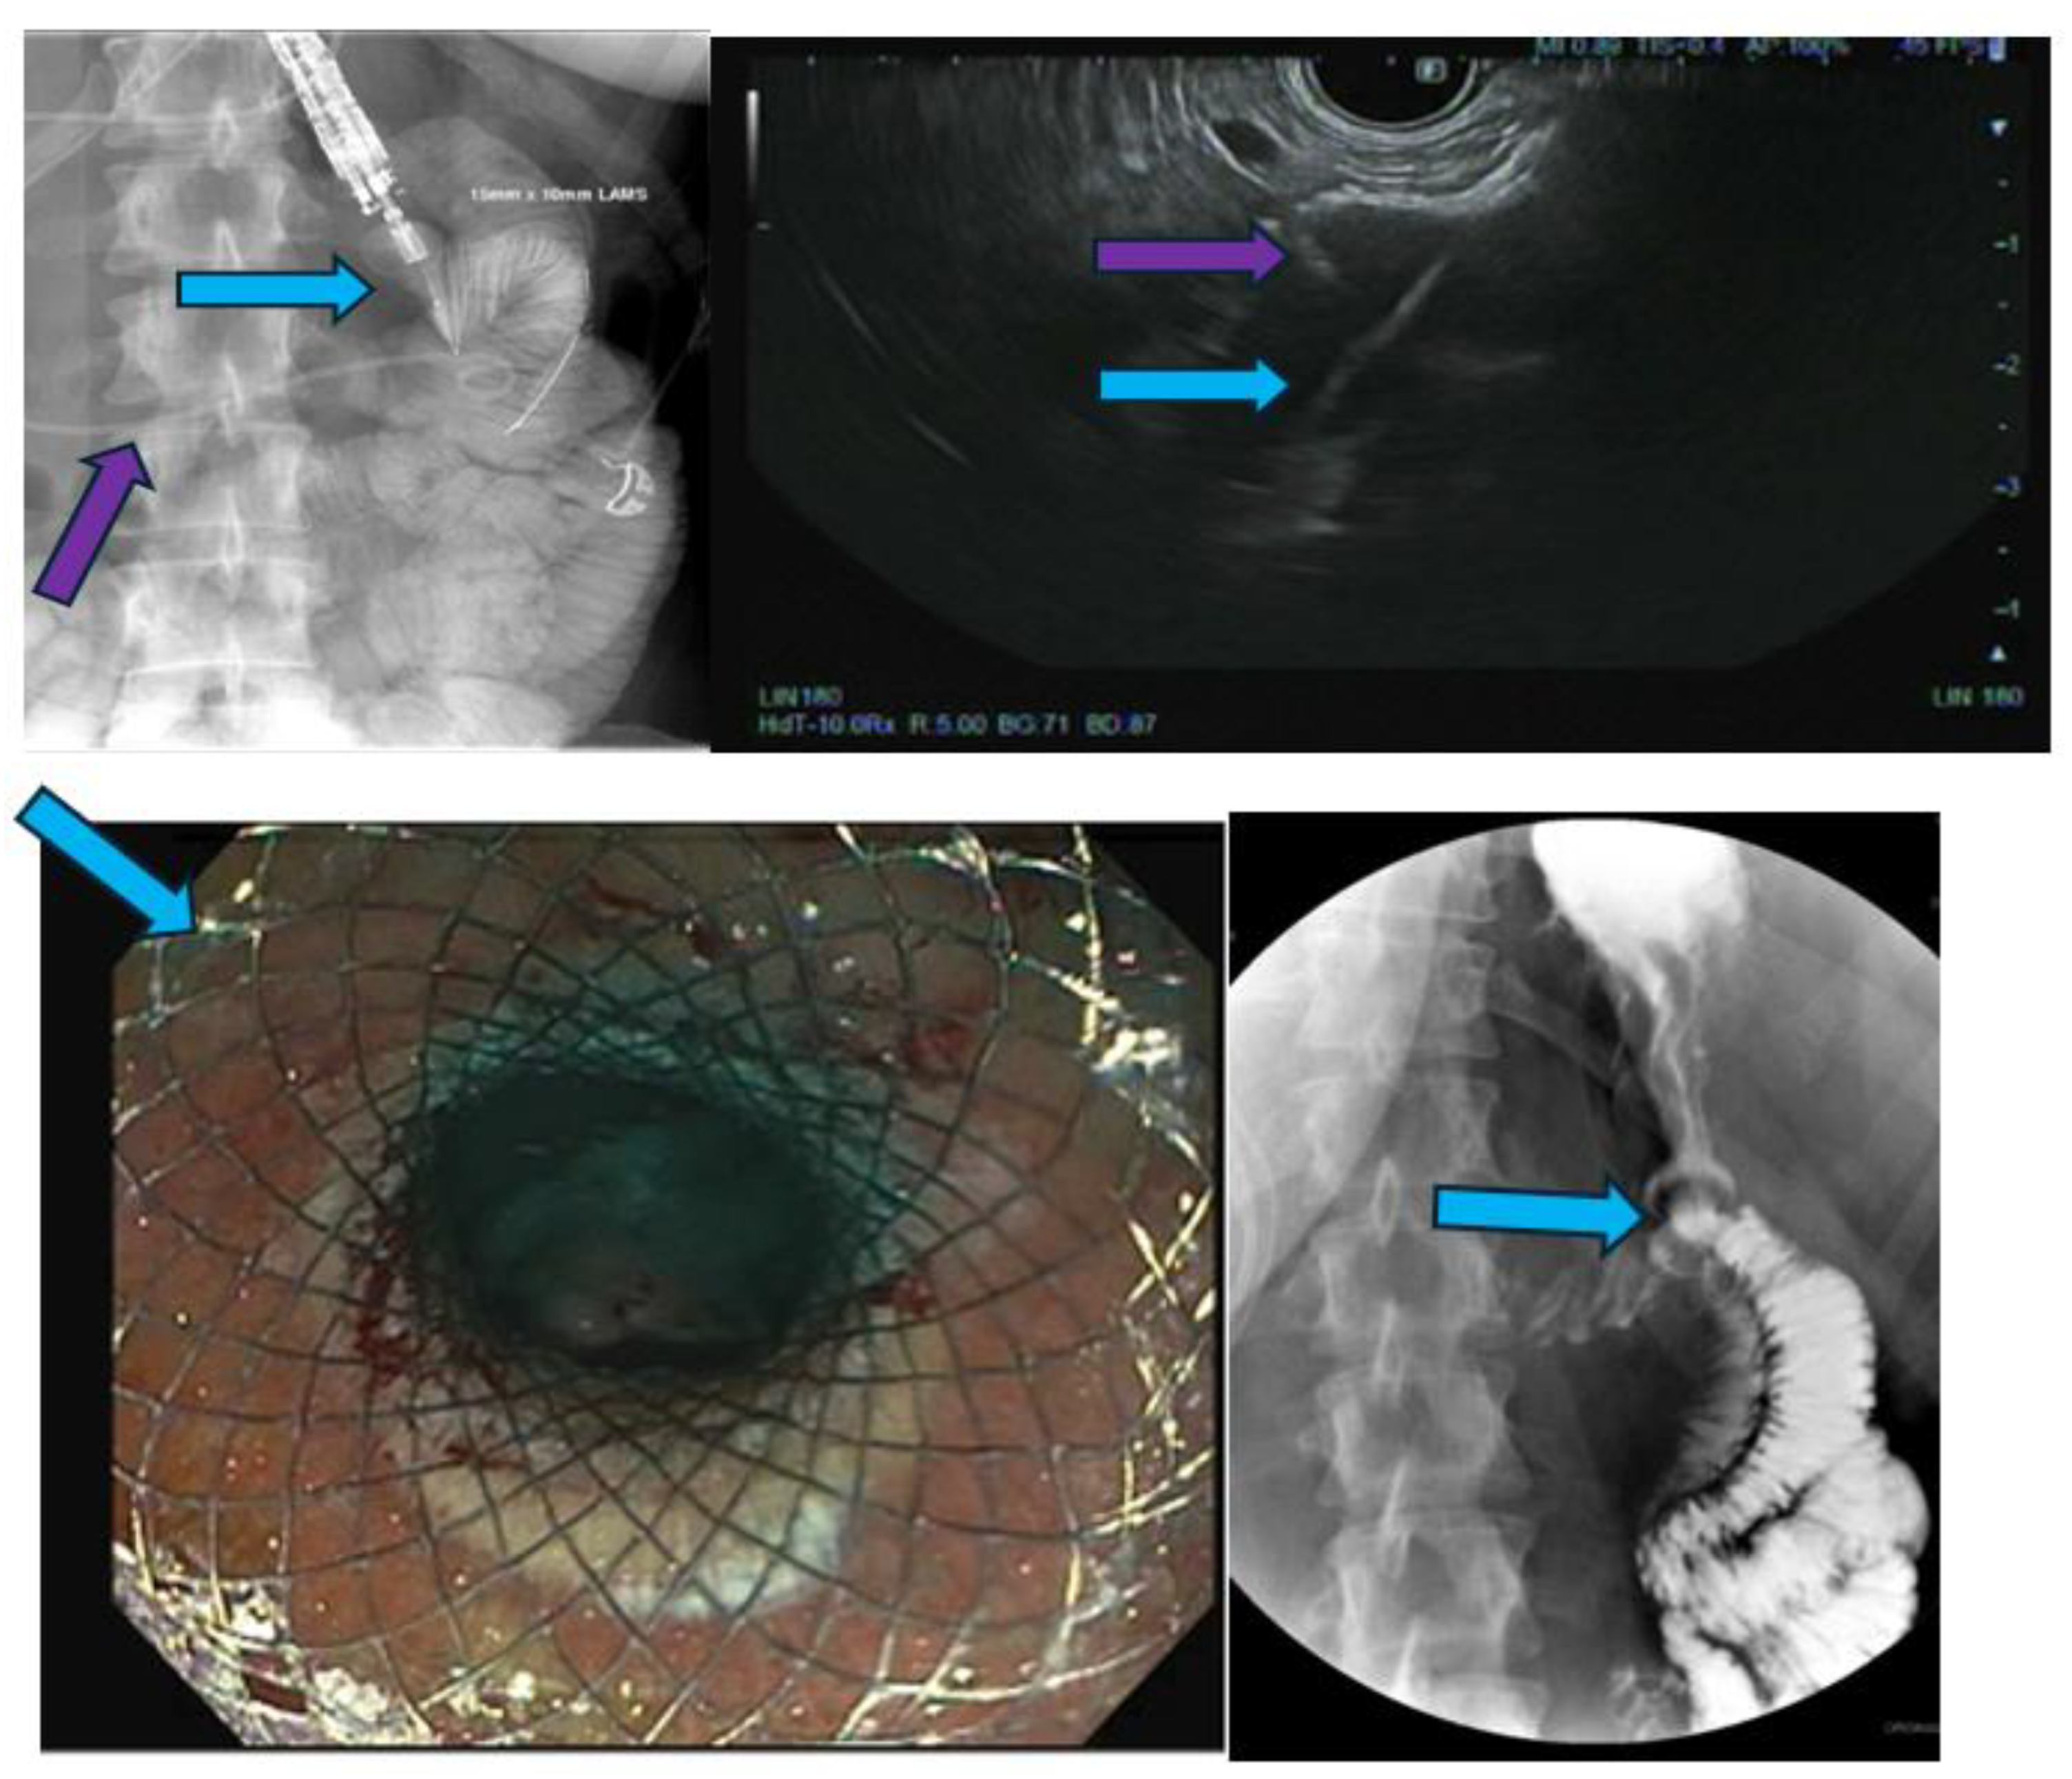

Pancreatic cancer is an aggressive malignancy, and the current 5-year survival rate in the United States, according to the Surveillance, Epidemiology, and End Results Program data, approximates 12%. Although the current standard for resectable pancreatic cancer most commonly includes neoadjuvant chemotherapy prior to a curative resection, surgery in the majority of patients has historically been palliative. The latter interventions include open or laparoscopic bypass of the bile duct or stomach in cases of obstructive jaundice or gastric outlet obstruction, respectively. Non-surgical interventional therapies started with percutaneous transhepatic biliary drainage (PTBD), both as a palliative maneuver in unresectable patients with obstructive jaundice and to improve liver functions in patients in whom surgery was delayed. Likewise, interventional radiologic techniques included placement of plastic and ultimately self-expandable metal stents (SEMS) through PTBD tracts in patients unresectable for cure as well as percutaneous cholecystostomy in patients who developed cholecystitis in the context of malignant obstructive jaundice. Endoscopic retrograde cholangiopancreatography (ERCP) and stent placement (plastic/SEMS) was subsequently used both preoperatively and palliatively, and this was followed by, or undertaken in conjunction with, endoscopic gastro-duodenal SEMS placement for gastric outlet obstruction. Although endoscopic ultrasound (EUS) was initially used to cytologically diagnose and stage pancreatic cancer, early palliation included celiac block or ablation for intractable pain. However, it took the development of lumen-apposing metal stents (LAMS) to facilitate a myriad of palliative procedures: Cholecystoduodenal, choledochoduodenal, gastrohepatic and gastroenteric anastomoses for cholecystitis, obstructive jaundice, and gastric outlet obstruction, respectively. In this review, we synopse these procedures which have variably supplanted surgery for the palliation of pancreatic cancer in this rapidly evolving field.